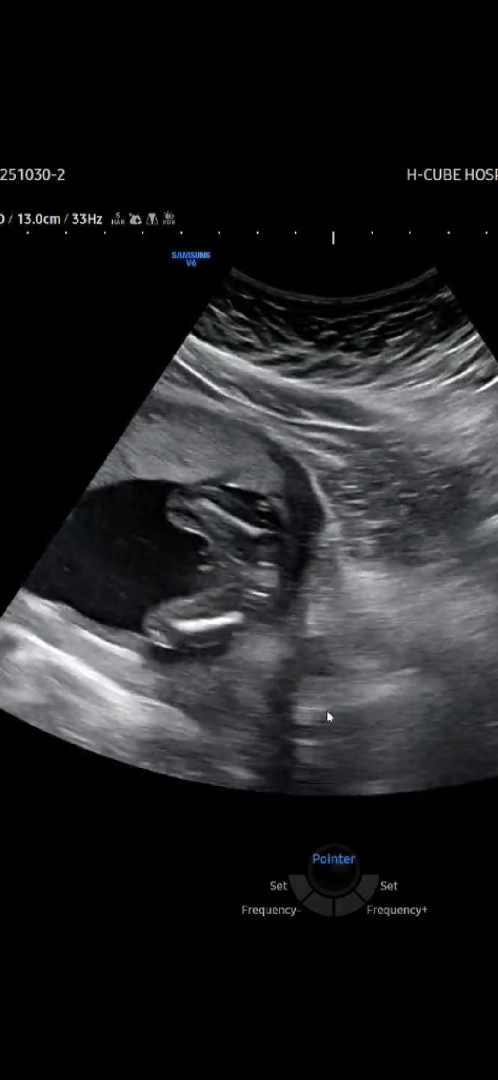

고츄인가요??16주차 초음파 ㅋㅋ

의사쌤이 확실하진 않은데 잘생겨보여~~ 이러셨는데 뭐가 보였으니까 이런말 하신거겠죠??

그런가바여... 동영상 친구들보여주니 삼각점 보인다네여.....ㅎ..